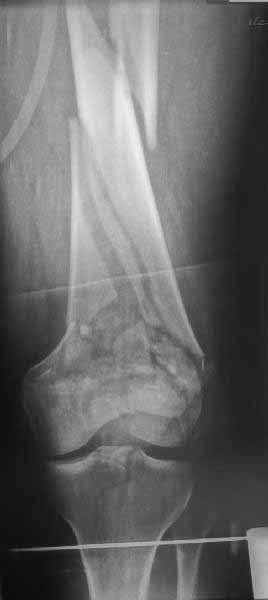

Рационально ориентироваться на качественный аспект - проблема или решается, или нет. Переломы типа 33C1 или C2 (то есть без фронтального раскалывания мыщелков, как на показанной Вами томограмме) при обычном качестве кости успешно можно фиксировать гвоздями с фронтальными винтами. Получается, их прочностных характеристик уже достаточно.

В приложении пример недавней операции, C3, открытая репозиция, фиксация мыщелков спицами и винтами, ретроградный синтез большеберцовым гвоздем 10,5 мм диаметром, винты 5 мм.